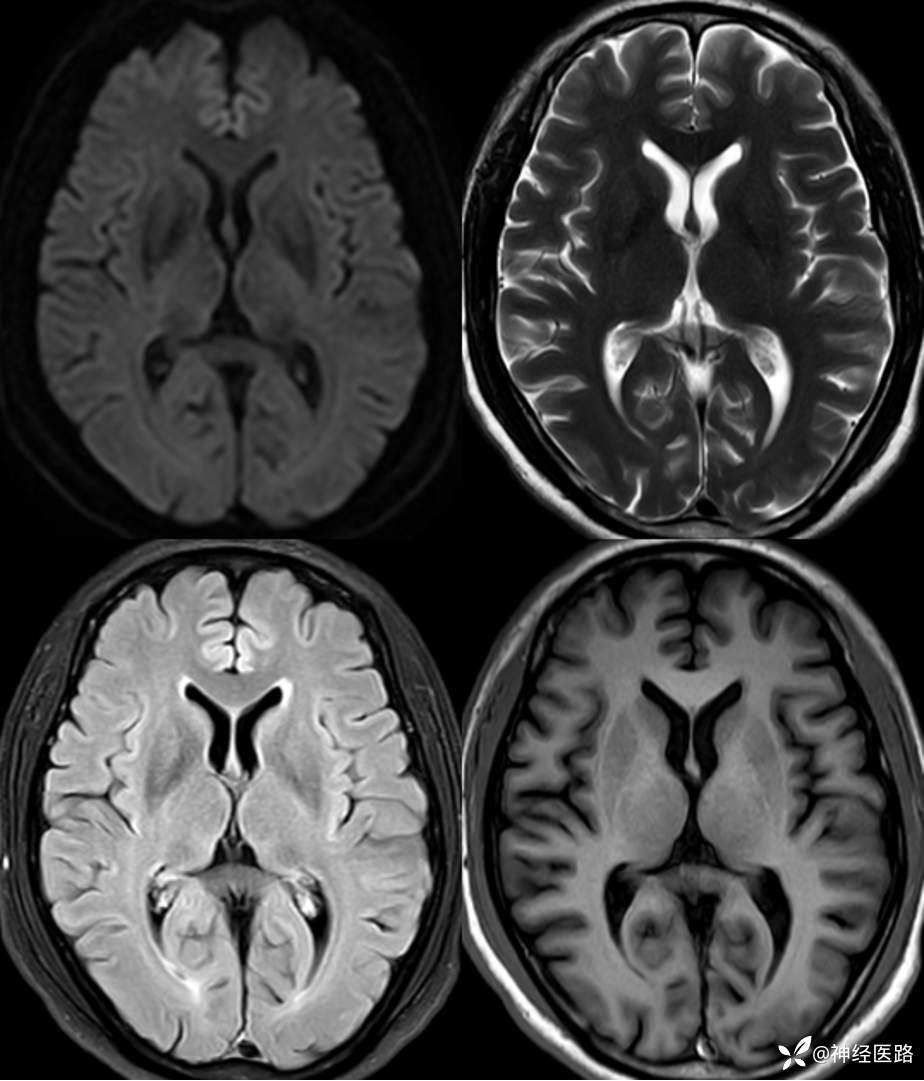

辅助检查:头部磁共振:1.颅脑DWI未见明显异常扩散受限。 2.脑白质高信号,脑萎缩。3.双侧上颌窦、双侧筛窦、双侧额窦炎。

补充1年余前直立倾斜试验、肌电图及头部磁共振检查资料。

两次影像对比